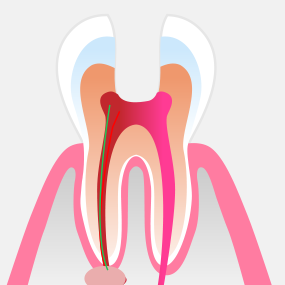

신경조직이 감염되거나 오염된 경우에는 신경치료가 필요합니다. 서울하나치과는 우수한 재료와 체계적인 치료 과정을 적용하여 안정적이고 높은 성공률의 신경치료를 제공합니다.

ROOT CANAL THERAPY

치주낭 길이 3mm 이하

치주낭 길이 3~5mm 이하

치주낭 길이 5~7mm 이하

치주낭 길이 7mm 이상